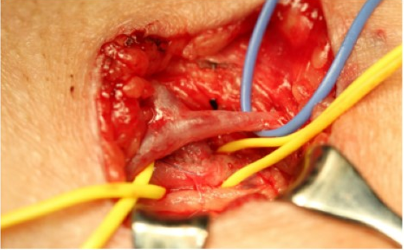

★ Case 3

静脉变异影响原手术方案

贵要静脉变异导致原“肱动脉-贵要静脉转位术”中转为“肱动脉-肱静脉转位术”